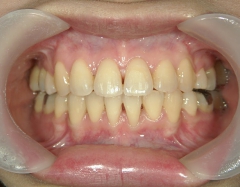

矯正歯科(全顎ワイヤー矯正)治療後

矯正歯科 治療後